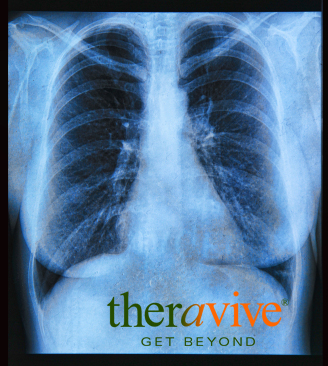

Also called bronchogenic carcinomas, lung cancers are divided into two broad categories - small cell lung cancer (SCLC) and non-small cell lung cancer (NSCLC). Small cell lung cancers occur less frequently are are the lung cancer most associated with cigarette smoking. SCLC occurs in 20% of lung cancer patients and is also the more aggressive form of the illness. Unfortunately, because of its rapid growth and metastasis, the discovery of SCLC often comes as a result of it already having spread to other parts of the body. NSCLC is the more common form of lung cancer, occurring in about 80% of cancer patients. Although also strongly associated with cigarette smoking, not all people who develop NSCLC are smokers. Adenocarcinomas are the most common of the non-small cell lung cancers, occurring in about 50% of NSCLC patients and develop in the outer areas of the lung. Squamous cell carcinomas are the next most common type of non-small cell lung cancers, accounting for about 30% of NSCLC cases and form in the central chest and bronchi. [2]

Lung cancer is also divided into developmental stages, although it has been suggested that these stages be redefined. NSCLC is divided into stages I through IV, stage I being the least severe and stage IV being the most advanced. Stage III of NSCLC is divided into substages. SCLC is divided into two stages, which are “limited” and “extensive”. [3]

Although great strides have been made in treating other forms of cancers, the prognosis for lung cancer is often grim. By the time of diagnosis, 65% of those diagnosed already have advanced stages of the disease. Surgery is the best option for those patients diagnosed with stages I through III, but as lung cancer is not always detected early, surgery becomes a less realistic option with the progression of the disease. For those with stage I NSCLC, the five year survival rate with surgery is 70%, but drops to only 30% for those with stage III. Stage IV lung cancer is quite simply classified as being inoperable. [4]